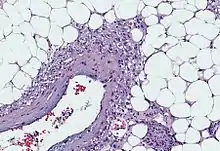

Angiomyolipomas are tumours consisting of perivascular epithelioid cells (cells which are found surrounding blood vessels and which resemble epithelial cells). A tumour of this kind is known as a PEComa, from the initials of perivascular epithelioid cell. Older literature may classify them as hamartomas (benign tumours consisting of cells in their correct location, but forming a disorganised mass) or choristoma (benign tumours consisting of normal cells in the wrong location). PEComas are themselves a kind of mesenchymal tumour which involves cells that form the connective tissue, cardiovascular, and lymphatic systems.[3]

An angiomyolipoma is composed of varying proportions of vascular cells, immature smooth muscle cells, and fat cells.[3] These three components respectively give rise to the components of the name: angio-, myo-, and lip-. The -oma suffix indicates a tumour.

Since all three components of an angiomyolipoma (vascular cells, immature smooth muscle cells, and fat cells) contain a "second-hit" mutation, they are believed to have derived from a common progenitor cell that developed the common second-hit mutation.[3]